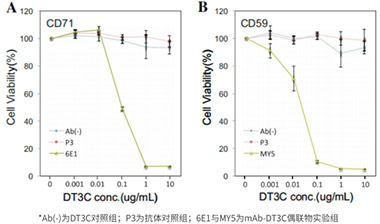

ADC(Antibody-Drug Conjugate)是由抗體和藥物連接而成的復合物,其中抗體用于特異性識別和結合腫瘤細胞表面的靶點,而藥物則用于殺死或抑制這些細胞。

查看詳情